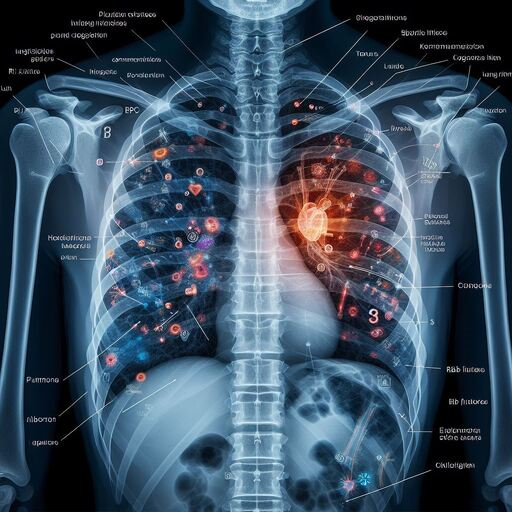

DeepInfinity.AI specializes in using advanced Generative AI and ML technologies to transform healthcare diagnostics and patient care. Our platform applies generative AI models for deep and accurate analysis of medical data, offering a range of predictive and diagnostic tools. These tools are designed to support healthcare professionals in making faster, more accurate diagnoses, thereby enhancing the overall quality of patient care. DeepInfinity.AI uses the advanced Generative AI technology to help Doctors, Hospitals and Diagnostic Centers & Labs etc.